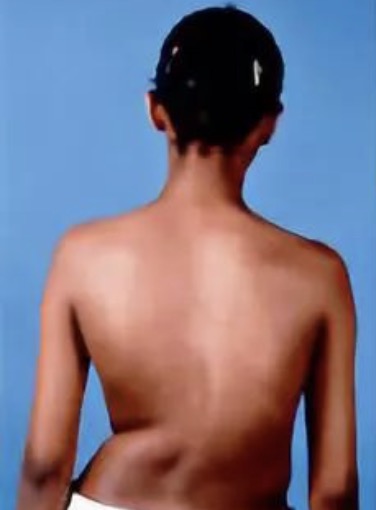

- 脊椎侧弯对健康的影响,除了体态外观上的问题外,多半会引起长期的腰背酸痛,另外脊椎关节在长期受力不均之下,可能发生退行性关节炎;如果侧弯持续增大,可影响心肺功能;非常严重的畸形也可能会压迫神经根和脊髓,引起瘫痪。对于脊柱侧弯,早期发现非常重要,家长有助于早期发现,那么,如何能早期发现孩子患有脊柱侧弯呢.....

- 脊柱侧弯学名脊柱侧凸,孩子患了脊柱侧凸,家长都比较着急,四处寻医,奔波折腾,心里没有底,小编组织了有关脊柱侧弯的一些问题,希望患者和家长正确认识,回归理性! 本期主要内容:认识脊柱侧凸,脊柱侧凸的病因、筛查常见的问题。 下期内容:脊柱侧凸研究进展、治疗方案、支具方面的问题。 文章来源: 国际.....